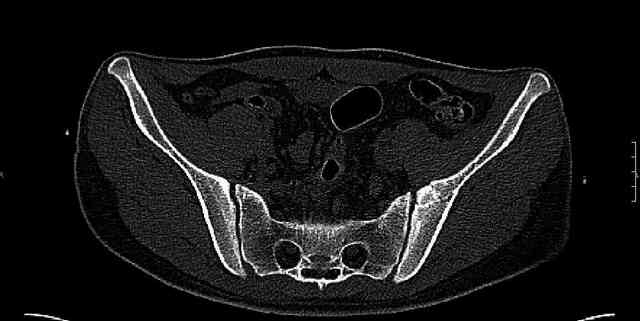

The last two images from the 3-D CT scan certainly makes the fracture look worse than the plan radiographs.

Some more images. Does it help to guess which part of the acetabulum is displaced?

Normal appearing SI joints and a healed posterior column limb... my bet's on caudal segment displacement.